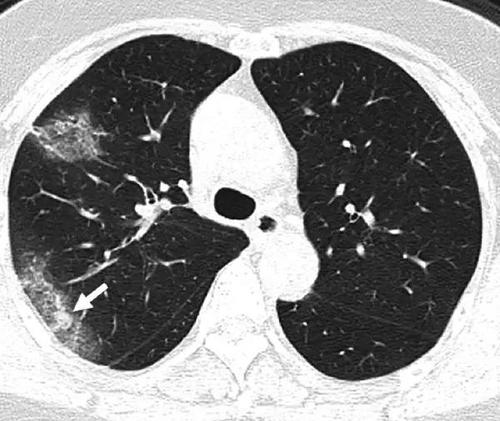

“Typically with ARDS, the lungs become inflamed. It’s like inflammation anywhere: If you have a burn on your arm, the skin around it turns red from additional blood flow. The body is sending it additional nutrients to heal. The problem is, when that happens in your lungs, fluid and extra blood starts going to the lungs. Viruses can injure cells in the walls of the alveoli, so the fluid leaks into the alveoli. A telltale sign of ARDS in an X-ray is what’s called ‘ground glass opacity,’ like an old-fashioned ground glass privacy window in a shower. And lungs look that way because fluid is white on an X-ray, so the lung looks like white ground glass, or sometimes pure white, because the lung is filled with so much fluid, displacing where the air would normally be.”